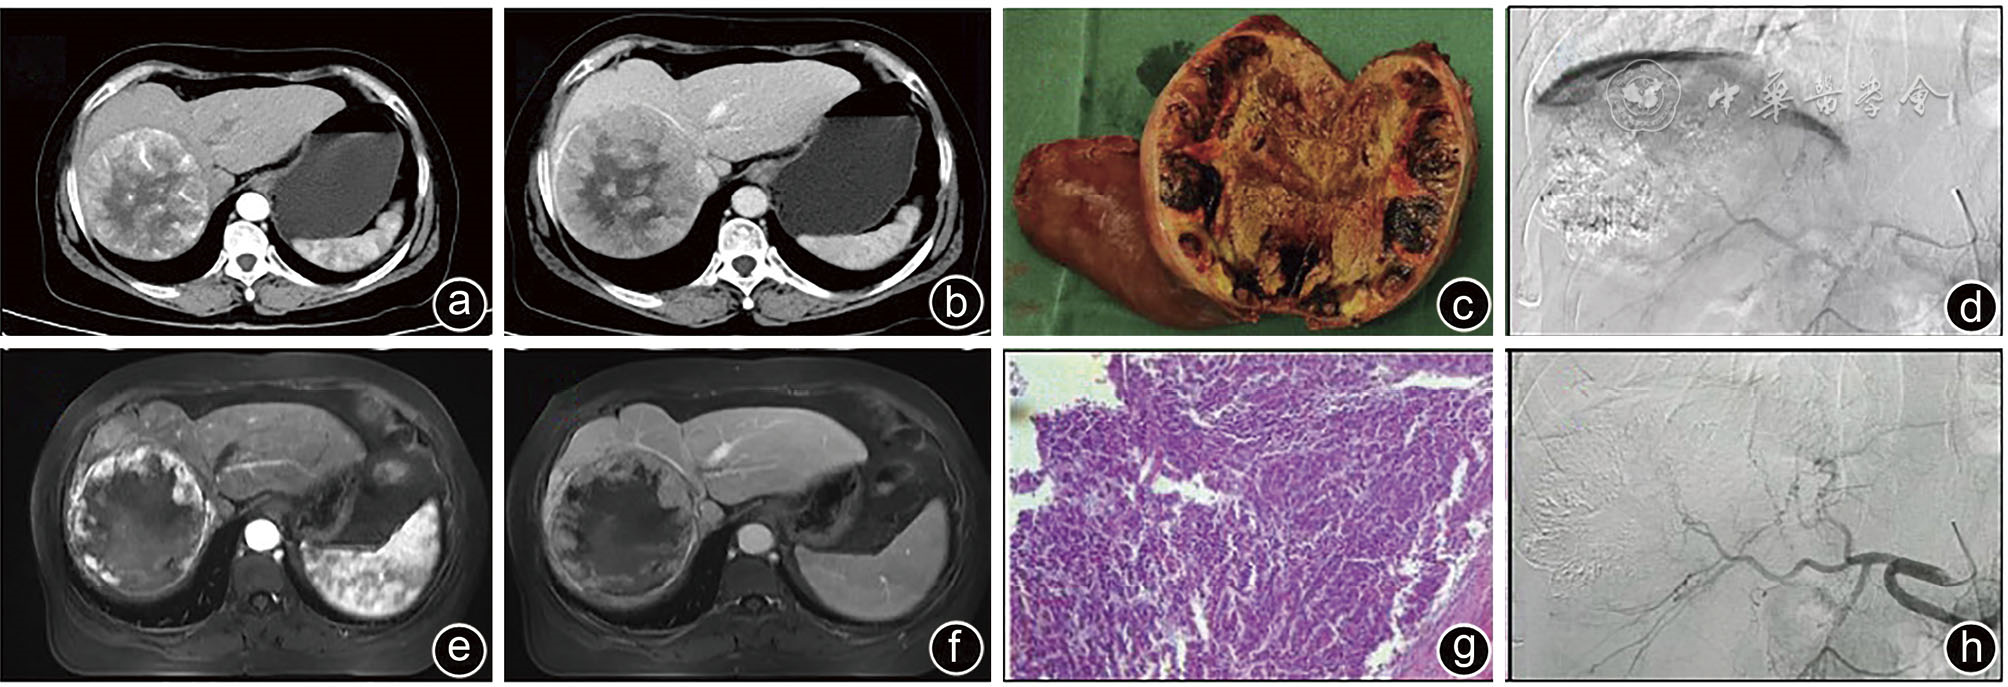

图2 巨块型肝癌患者DEB-TACE典型治疗情况 注:a、b为DEB-TACE治疗前CT示肿瘤明显强化;c、g为术后标本及病理(HE,×100),提示肿瘤大部分(>90%)坏死;d、h为拒绝手术患者动脉造影提示达CR;e、f为DEB-TACE治疗后CT示肿瘤PR;DEB-TACE为载药微球TACE,PR为部分缓解,CR为完全缓解